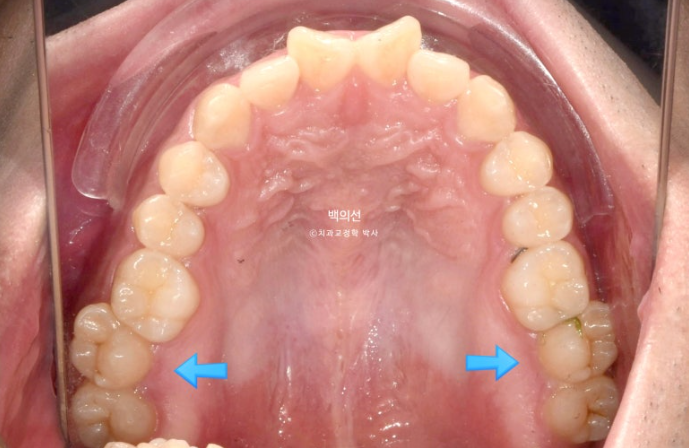

앞니가 삐뚤하고 소위 나비치아 입니다. 맨 뒤 큰어금니가 바깥으로 덧니처럼 뻗쳐있습니다.

교합면 사진에서 나비치아와 바깥으로 나가있는 두번째 큰어금니가 잘 보입니다.

파란 화살표 치아끼리 엇갈려 물리는 가위교합으로 교합이 안되는 상태입니다.